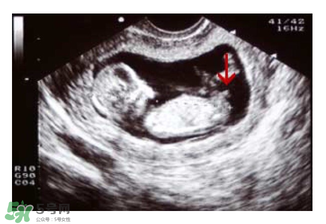

必須要NT超圖全景,可以看到下半部分的B超圖片才能判斷。外國(guó)人稱這種判斷法為nub theory。

主要通過尾椎那里判斷。 為了讓大家更直觀一些,我找兩個(gè)比較明顯的圖,男左女右,大家看男孩兒的特征點(diǎn)與身體呈45度角,還多一些,而女孩兒的特征點(diǎn)幾乎和軀體平行。圖第一張男寶,第二張女寶

用線條表示一下就更直觀了.當(dāng)然,這也不是完全絕對(duì)的,如果你們發(fā)現(xiàn)自己的寶貝兒與心想的不一樣,那這理論不一定對(duì),不是絕對(duì)的.千萬不要因?yàn)檫@個(gè)而影響自己孕期心情,寶寶健康是第一位的,我只是把自己所了解到的知識(shí)給大家普及一下。